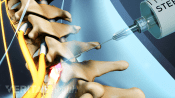

Injections relieve neck and back pain by delivering medications directly to the affected area, reducing inflammation.